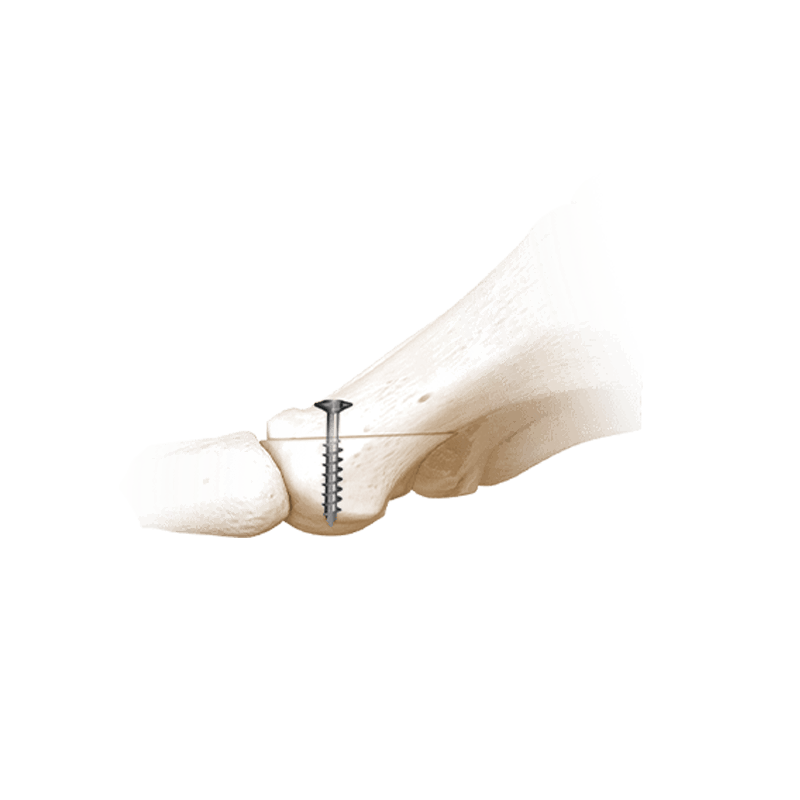

Fixation Devices - Compression Hardware

IBS™-B Beveled Screw System

IBS™-B Beveled Screw System delivers the strength, control, and versatility your MIS workflow demands.